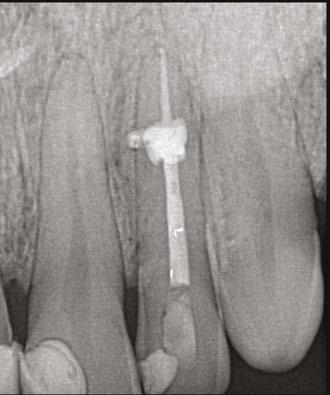

A 41-year-old male presented with a chief complaint of pain and swelling adjacent to tooth No. 10. The patient reported a history of trauma as a teenager, though he had not experienced issues until the recent onset of pain and swelling. Clinical examination revealed tenderness on the buccal gingiva around tooth No. 10, with sensitivity to percussion and biting. A small, fluctuant intraoral swelling was noted near the apex of tooth No. 10, and the tooth did not respond to vitality testing. Radiographic examination showed a large perforating internal resorptive defect near the apical third of the root (Figure 3A). CBCT (Veraviewepocs 3D R100; J. Morita) revealed significant alveolar bone loss adjacent to the defect, extending along the entire mesial side of

Figures 2A-2D: 2A: Periapical radiograph of tooth No. 21. Large resorptive defect is noted in external cervical region. Blue arrows point to a thin layer of predentin that appears to be running through defect. Outline is what remains of root canal wall. Tooth tested vital, and diagnosis of invasive cervical root resorption was made. Due to minimal remaining tooth structure, extraction was advised. 2B-2D: Sagittal, coronal, axial slices show resorptive defect external to root canal

the apical half of the root of tooth No.10 and reaching the root of tooth No. 9 (Figures 3B and 3C).

A diagnosis of pulpal necrosis with acute apical abscess was made. All treatment options, including extraction with replacement by an implant or bridge, were discussed. The patient, motivated to retain the tooth, opted for root canal therapy and repair of the resorptive defect. Informed consent was obtained.

First visit

The patient was anesthetized with 1.7 mL of 4% articaine with 1:100,000 epinephrine (Septocaine®; Septodont®, Lancaster, Pennsylvania) via labial infiltration. Rubber dam isolation was achieved, and the tooth was accessed using a No. 2 surgical length carbide round bur. Necrotic pulp was encountered. Working length was established with a Root ZX® apex locator (Morita, Tokyo, Japan), and the canal was instrumented to a size 35 .04 Vortex Blue® rotary file (Dentsply Tulsa Dental, Johnson City, Tennessee). Care was taken to ensure that the files passed through the resorptive defect and entered the apical portion of the canal. The canal was irrigated with 5.25% sodium hypochlorite, and the EndoActivator® (Dentsply, Tulsa, Oklahoma) was used to sonically agitate the irrigant to promote thorough disinfection of the resorptive defect. The canal was dried with paper points, and calcium hydroxide (Ultracal™ XS, Ultradent Products Inc, South Jordan, Utah) was syringed into the canal and the defect. The tooth was then temporarily restored with Cavit® (3M ESPE, Neuss, Germany).

Second visit

Two weeks later, the patient returned for completion of the endodontic treatment, reporting that all symptoms had subsided. Clinical examination confirmed that the swelling had resolved. Calcium hydroxide was removed from the canal through instrumentation, irrigation, and activation with the EndoActivator. The canal was dried with paper points, and excess irrigant was removed using surgical suction with a micro-tip. A master gutta-percha cone was placed to the working length and confirmed with radiographic examination (Figure 3D). The canal was coated with EndoSequence® BC (bioceramic) sealer (Brasseler USA, Savannah, Georgia) to ensure sufficient sealer filled the resorptive defect. It was then obturated with gutta percha and BC sealer using the technique of warm vertical condensation (Figure 3E). The lingual access opening was restored with TPH Spectra® ST composite (Dentsply Sirona, Charlotte, North Carolina), and the patient was scheduled for recall to monitor healing.

At 1-year, 2-year, and 5-year recall visits, the patient was asymptomatic, and radiographs showed complete healing with full restoration of bone and lamina dura adjacent to the resorptive defect (Figures 3F and 3H). The patient expressed satisfaction with the outcome, having retained a tooth originally planned for extraction.

Figures 3A-3H: 3A. Preoperative periapical radiograph of tooth No.10 showing internal root resorption in apical third of root. There is significant alveolar bone loss adjacent to defect. 3B. Sagittal CBCT image of tooth No. 10 showing internal resorptive defect perforating on mesial aspect of root. Note adjacent alveolar bone loss extending proximally to tooth No. 9. 3C. Axial CBCT image of internal resorptive defect perforating on mesial aspect of root. There is thin layer of circumferential dentin remaining and extensive alveolar bone loss adjacent to the defect. 3D. Periapical radiograph showing gutta-percha cone fit. Gutta-percha cone passes through resorptive defect to contact apical portion of root canal. 2E. Immediate postoperative periapical radiograph of tooth No.10 once root canal was completed and resorptive defect was restored. 2F. Two-year follow-up showing complete healing of radiolucency adjacent to defect and reestablishment of PDL. 2G. Two-year follow-up CBCT. Coronal slice showing complete healing of radiolucency adjacent to defect and reestablishment of PDL. 2H. Five-year follow-up radiograph. Patient is completely asymptomatic